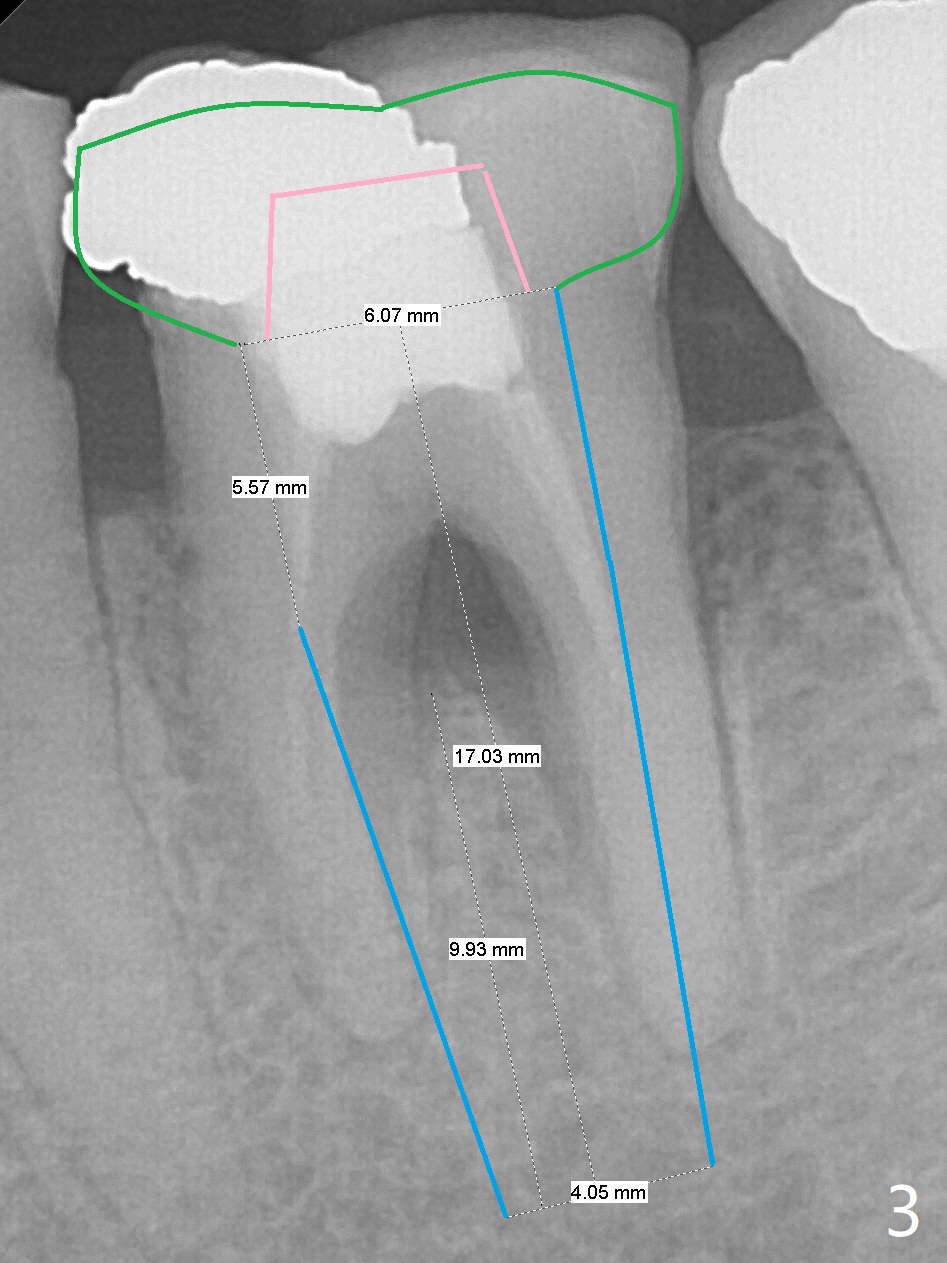

A 54-year-old man has several restoration with sign of bruxism (Fig.1). The tooth #19 has mesiodistal crack with furca radiolucency (Fig.2 *). To prevent abutment screw loosening associated with heavy mastication, a 6x17 mm tissue-level implant will be placed free hand due to the patient's tight schedule (blue, Fig.3,4,5). Pink: abutment; green: restoration which will be seated partially in the implant to reduce abutment loosening. To reduce possible neuropathy and have freedom to place implant deep, the implant length will be shorter, 14 mm, if the bone is dense. Take photos to show the crack line and buccal swelling. The patient returns for implant 4 months post extraction without bone graft in his home country with bone loss (Fig.6). In the presence of the accessory canal (Fig.7 *), a 5x10 mm implant is safe to be placed.